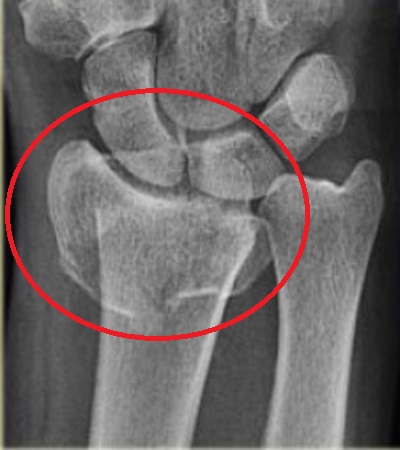

Η οστεοπόρωση είναι μια σιωπηρή νόσος, δεν παρουσιάζει συμπτώματα για μεγάλο χρονικό διάστημα. Αυτό σημαίνει ότι περνάνε αρκετά χρόνια, κατά τη διάρκεια των οποίων η οστεοπόρωση συνεχώς χειροτερεύει από πλευράς απώλειας οστικής μάζας και διαταραχής της μικροαρχιτεκτονικής δομής των οστών, μέχρι να εμφανιστεί το πρώτο της σύμπτωμα, που είναι το κάταγμα. Η οστεοπόρωση είναι νόσος όλων των οστών και γι’ αυτό κατάγματα μπορεί να συμβούν σε διάφορες θέσεις του σκελετού, αλλά συνήθως συμβαίνουν στους σπονδύλους, στον αυχένα του μηριαίου οστού και στο αντιβράχιο. Πιο συγκεκριμένα, περίπου 40% των οστεοπορωτικών καταγμάτων αφορούν τη σπονδυλική στήλη, 20% τον αυχένα του μηριαίου οστού, 20% το αντιβράχιο και 20% διάφορα άλλα οστά. Τα κατάγματα του αυχένα του μηριαίου οστού και του αντιβραχίου συμβαίνουν πάντοτε μετά από έναν χαμηλής βίας τραυματισμό, όπως είναι η πτώση από την όρθια θέση, ενώ συνοδεύονται πάντοτε από πόνο. Αντίθετα, τα σπονδυλικά κατάγματα συμβαίνουν συχνά χωρίς να προηγηθεί τραυματισμός και αρκετές φορές δεν συνοδεύονται από πόνο στη ράχη ή στη μέση παρά μονάχα από ένα ελαφρύ αίσθημα καύσου. Απώλεια ύψους και κύφωση αποτελούν όψιμες εκδηλώσεις της οστεοπόρωσης και οφείλονται σε σπονδυλικά κατάγματα.